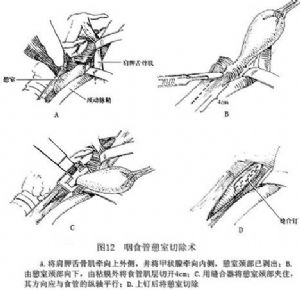

在局麻下沿左側胸鎖乳突肌內側作切口(圖10),暴露咽部及頸段食管,注意保護喉返神經。有Zenker憩室時,對環嚥肌的定位有助。對於較小的憩室可只作環咽肌切開術(圖11)。如憩室中等大小,可將之充分遊離,倒轉後固定縫合在脊柱前筋膜上。如憩室過大或懸吊後過分臃腫,則應將之切除(圖12)。